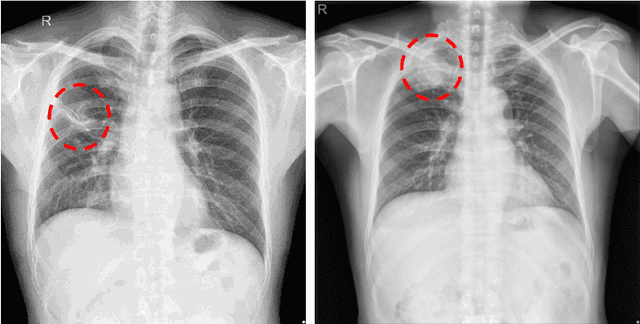

Abstract:Chest X-ray (CXR) is the most common examination for fast detection of pulmonary abnormalities. Recently, automated algorithms have been developed to classify multiple diseases and abnormalities in CXR scans. However, because of the limited availability of scans containing nodules and the subtle properties of nodules in CXRs, state-of-the-art methods do not perform well on nodule classification. To create additional data for the training process, standard augmentation techniques are applied. However, the variance introduced by these methods are limited as the images are typically modified globally. In this paper, we propose a method for local feature augmentation by extracting local nodule features using a generative inpainting network. The network is applied to generate realistic, healthy tissue and structures in patches containing nodules. The nodules are entirely removed in the inpainted representation. The extraction of the nodule features is processed by subtraction of the inpainted patch from the nodule patch. With arbitrary displacement of the extracted nodules in the lung area across different CXR scans and further local modifications during training, we significantly increase the nodule classification performance and outperform state-of-the-art augmentation methods.